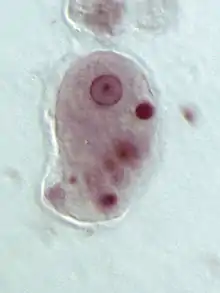

E. histolytica, a parasite that is very common among children in Guatemala[21]

It has been seen that the prevalence of parasites is significantly higher among younger children and those who are malnourished.[18]:35 Parasites are usually transferred through contaminated water, making them dangerous because they are able to induce malnutrition by consuming the body's nutrients, thus impeding a child's physical development.[22]:97 For school children who are infected with parasites, cognitive functioning can drastically decrease, directly impacting their education.[23] School children who have been treated for parasites immediately perform significantly better in school settings. Parasite infections can also vary based on access to clean water and whether or not sewage disposal is present.[18]:38 The Millennium Development Goals discussed the importance of deworming to help meet the goals set by the United Nations.[24] Parasites can have serious long-term consequences in that they directly affect development and health for decades after. However, inexpensive, single-dose medications exist that can fully treat these parasitic infections.[24]